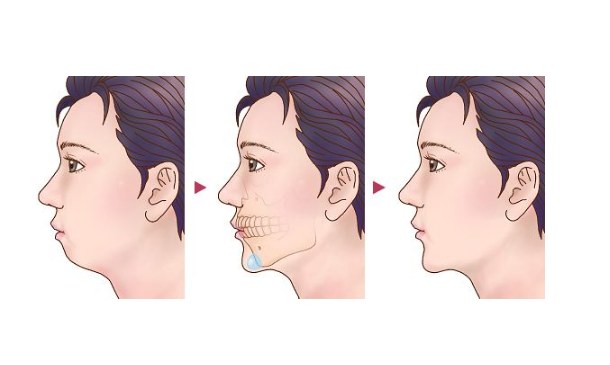

牙顎畸形圖片

牙槽骨突出

牙槽骨突出

牙槽骨突出

牙槽骨突出

牙槽骨突出

牙槽骨突出

牙槽骨突出

牙槽骨突出

牙槽骨突出

牙槽骨突出

牙槽骨突出

牙槽骨突出

牙槽骨突出

牙槽骨突出

牙槽骨突出

牙槽骨突出

牙槽骨突出

牙槽骨突出

牙槽骨突出

牙槽骨突出